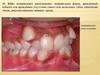

Ихтиоз -это наследственное заболевание кожи, протекающее по типу

дерматоза. Характеризуется диффузным нарушением ороговения и

проявляется в виде чешуек на коже, которые напоминают рыбью чешую.